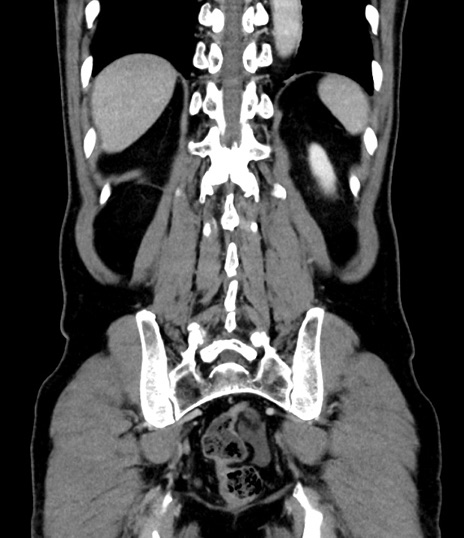

横断像